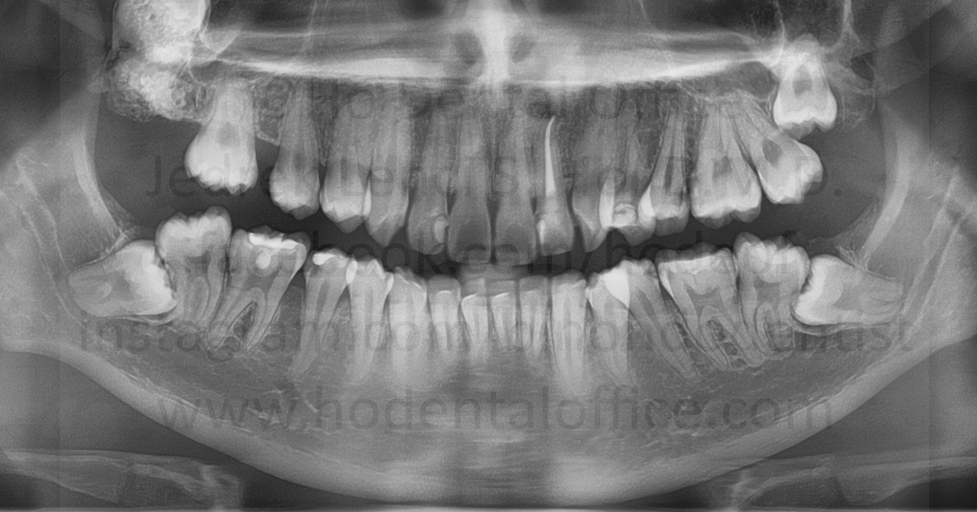

| examples of operculum located on lower third molars | |

Possible consequences of leaving an operculum intact includes, but not limited to:

- pericoronitis - inflammation of the gum specific to the area on top of the dental crown, maybe due to food debris becoming stuck and uncleanable

- dental cavities - due to food debris becoming stuck and uncleanable underneath the operculum

- traumatic contact - the operculum may be bitten by opposing tooth, causing injury